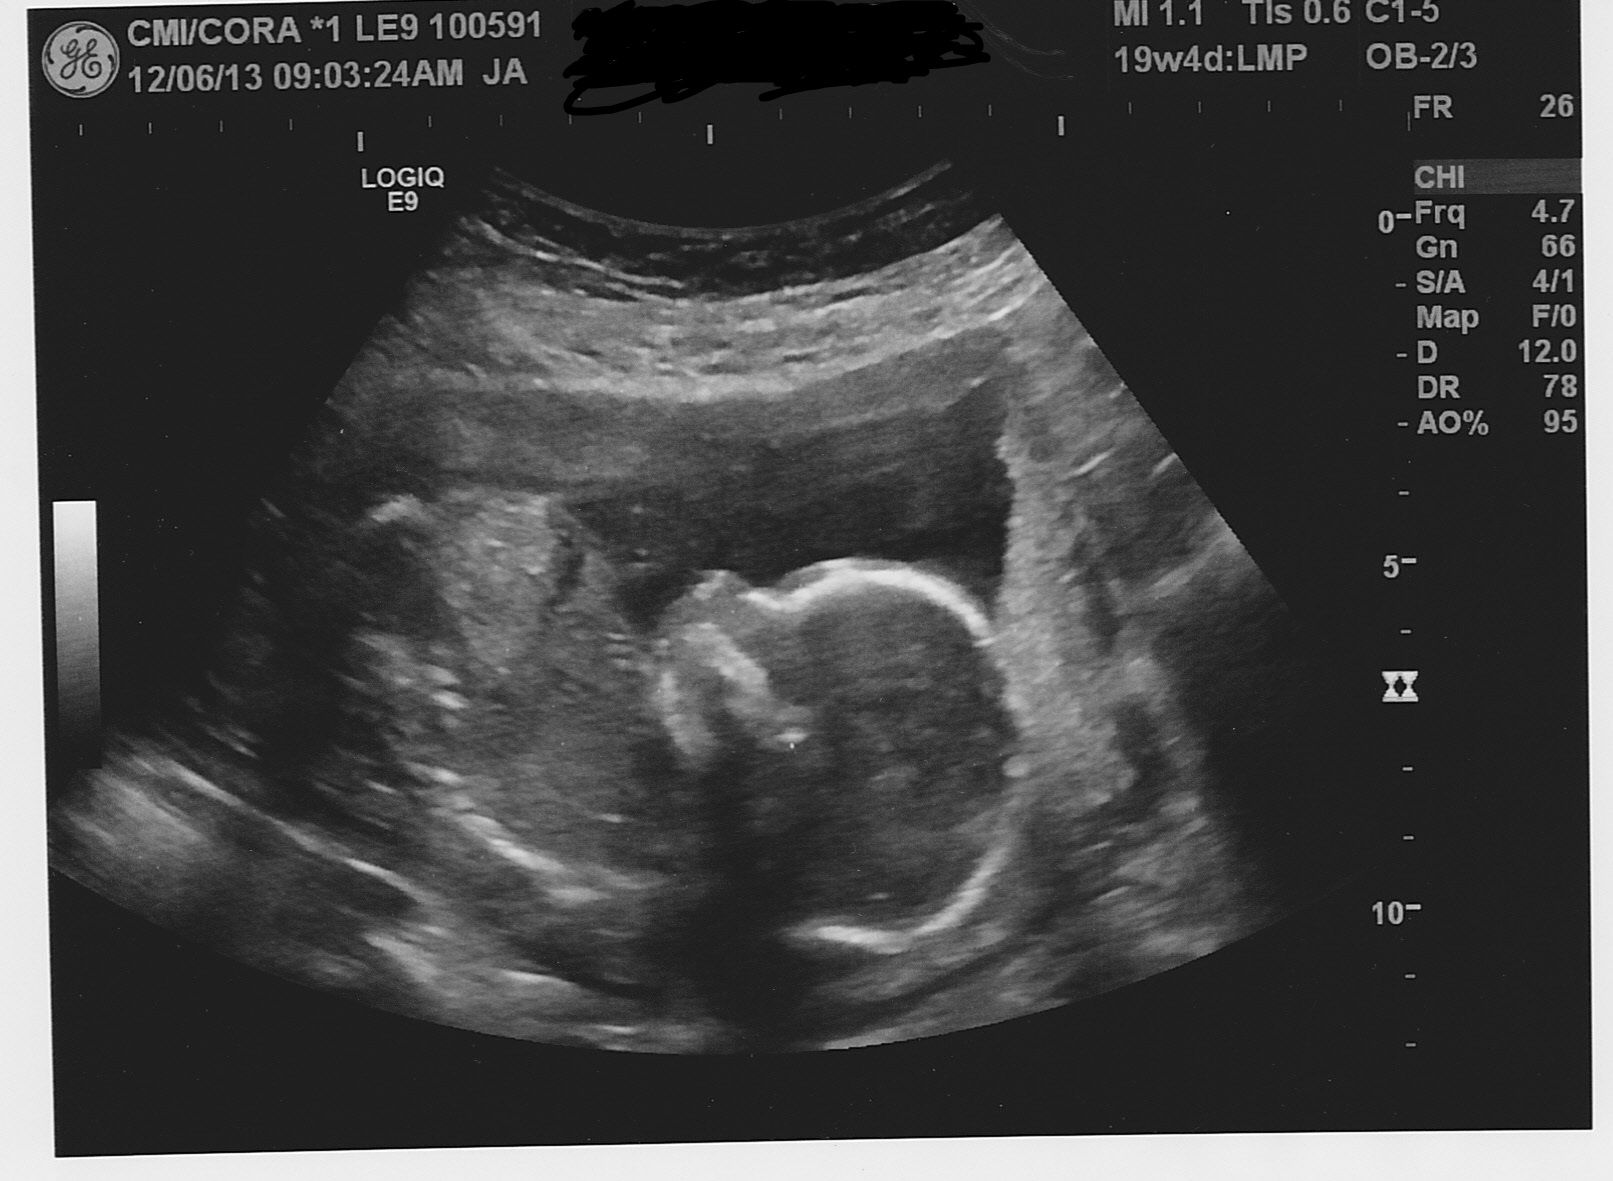

In between appts right now, but so far so good! We are measuring only 1 day behind my LMP but 5 days ahead of my dating U/S at 8w. Baby James was snuggled up facing away from us, but she also guessed "about 90% boy". So I'm sticking with it! All organs have formed and no extra limbs in there (which I was having nightmares about). Plus, we have a strong heartbeat of 153 and he was kicking away in there!

Our junior is measuring about 7 days ahead of my due date and is absolutely perfect in every way. They put our ultrasound on a DVD and I watched it again last night just absolutely in awe of how much they can see and determine from an ultrasound. I feel blessed to have such amazing technology available. I loved watching his little hands up around his face and seeing his little legs and feet. I can't wait for April to come so I can hold him in my arms.